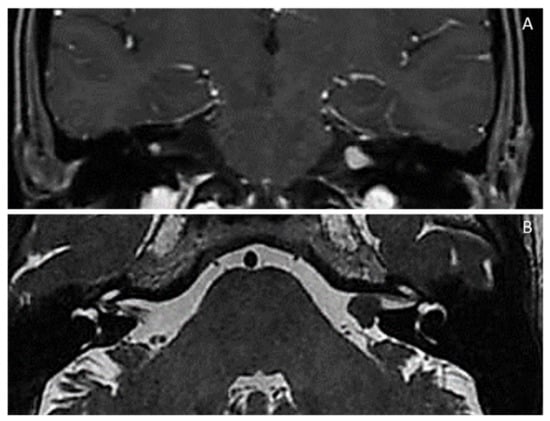

| NF2-related schwannomatosis [NF2/MERLIN-schwannoma predisposing syndrome (NF2/MERLIN-SPS)] (Previously, neurofibromatosis type 2 or NF2) [MIM # 101000; ORPHA:637] Chromosome 22q12.2 (NF2/MERLIN moesin-ezrin-radixin-like gene): identical NF2 gene pathogenic variant in at least two anatomically distinctNF2related tumours (e.g., schwannoma, meningioma and/or ependymoma); NF2 gene variants in unaffected tissues (e.g., blood) and major/minor criteria (see below); Main features: (1) Gardner type (adulthood): Bilateral (or, sometimes, unilateral) VIII cranial nerve (vestibular) schwannoma(s) *; schwannomas of cranial nerves *; multiple meningiomas, ependymomas, schwannomas *; early-onset (posterior subcapsular or cortical) cataracts *; skin schwannomas (NF2 plaques) *; nodular schwannomas *; (2) Wishart (severe) type (childhood): prior to appearance of VIII nerve schwannomas * and/or nervous system tumours (meningiomas, ependymomas) *, non-VIII-cranial nerve schwannomas (e.g., mixed nerves, V, VII) *; early-onset (posterior subcapsular or cortical) cataract *; epiretinal membranes/hamartomas *; skin schwannomas (NF2 plaques) * diffused over body; brain cortical dysplasia; bone dysplasia; (3) Congenital type (neonatal/< 1 year): small bilateral VIII nerve schwannomas * stable for decade(s); optic nerve sheath meningioma(s) *; epiretinal membranes/hamartomas *; early-onset (posterior subcapsular or cortical) cataract *; skin schwannomas (NF2 plaques) * in atypical places (face, arms, legs) later disappearing; ependymomas *; spinal cord schwannomas and meningiomas *; brain cortical dysplasia; |

| Mosaic (segmental)NF2-related schwannomatosis [Mosaic NF2/MERLIN-schwannoma predisposing syndrome] (Mosaic NF2/MERLIN-SPS) (Previously, mosaic neurofibromatosis type 2 or mosaic NF2) [MIM # 101000; ORPHA:637] Chromosome 22q12.2 (NF2/MERLIN moesin-ezrin-radixin-like gene): NF2 gene pathogenic variant (variant allele fraction) in unaffected tissue (e.g., blood) < 50% Main features: NF2 stigmata distributed in a segmental/localised (mosaic) distribution(e.g., unilateral VIII nerve schwannoma, ipsilateral meningiomas, schwannomas); Diagnosis ➔ NF2 gene pathogenic variant in unaffected tissue (e.g., blood) < 50% |